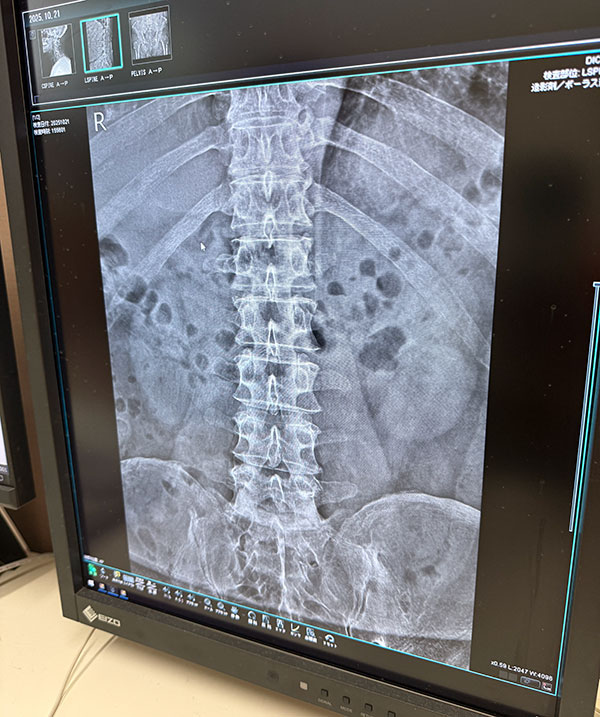

| 2025/10/21火 楓の森で検査 ↓前 次↑ 朝イチ女王送ってクルっとひさ枝へ。 ![]() 8:30ぐらいですが少し落ち着いてきたのかな。 ![]() 姉やんから頼まれたお土産うどん買いがてらでしたが久々釜玉かけを。うむ、自分にとってのこの店はやっぱこれやな。 ![]() 主治医モリケン先生のトコにも行きます。受付の美女に「いつもの膝ですか?」→「はい、それに加え腰と尻と首と。。」→「事故か何かで?」→「いや転んだと言うか。。」→「いつですか?→「10/18土です」てか 「先生も知ってますので」 ※その場にいたw というやりとりをしました!レントゲン撮ってもらいました。 ![]() ドキドキしながら結果を。 ![]() 首は一箇所狭まってるそうで、今回のが原因ではなく加齢とのこと。ヨシキよりかはマシでしょう。 ![]() ヒビ等はないようです。 ![]() 椎間板はもうすぐヘルニアかもやけど、それは元々やからなあ。 ![]() パイプ椅子で頭打ったけどそれなかったらもっとヤバかったかもとのことでした、ともかくHOTしつつ 正式に椅子アクションを禁止 ※ジャンプもデス されました。新しい面白いコトを探しましょう。 ![]() いつもの膝ヒアルロン酸デュアル打ってもらって後に。 ![]() ひさ枝でもらった麺で寄せ鍋ですか。 ![]() 土曜のライブや日曜からの九州出張までに痛さマシになってて欲しい。 ↓前 次↑ | ||